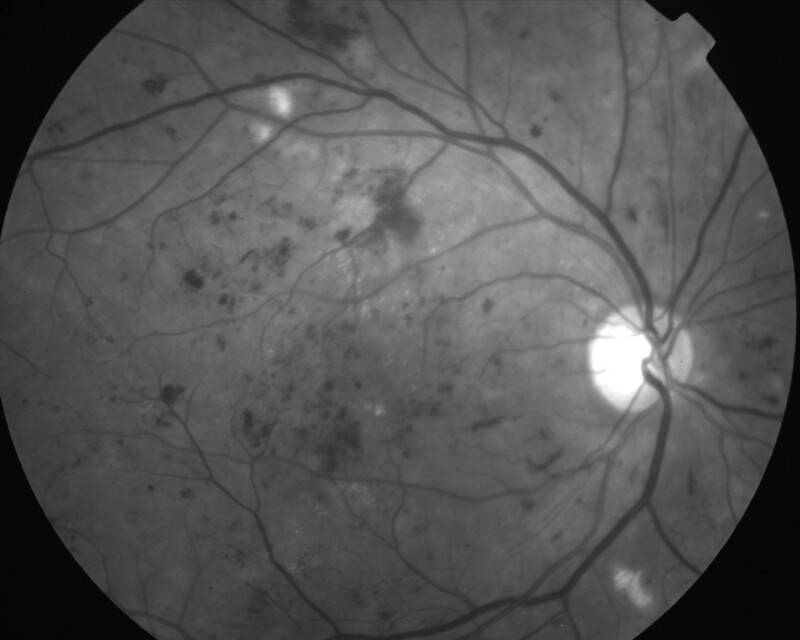

RETINOPATHIE DIABETIQUE NON PROLIFERANTE SEVERE

IMG0001.JPG